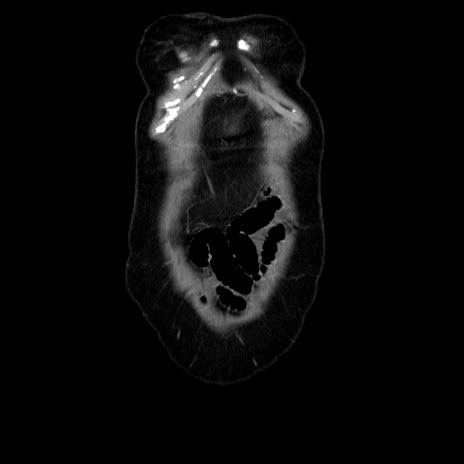

横断像

【症例】70歳代女性

【主訴】お腹が張る

【現病歴】1週間くらい前から腹部膨満の自覚あり。昨日夜から増悪したため、本日救急外来受診。

【身体所見】意識清明、BT 36.5℃、BP 165/106mmHg、HR 80bpm、SpO2 98%、腹部:膨満、軟、自発痛・圧痛なし、触診にて不快感あり、腸蠕動音:減弱

【データ】WBC 12600、CRP 1.04